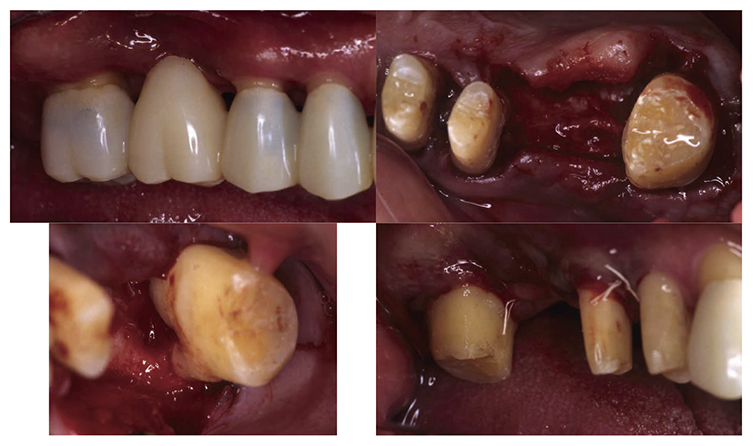

3) Periodontal surgical therapy

At the reevaluation examination after completion of basic periodontal treatment, deep periodontal pockets and grade 2 furcation involvement were observed. Therefore, in April 2010 (age 42), enamel matrix proteins were applied in a procedure for periodontal regeneration (Fig.4),and in June of the same year, gingival flap operation and distal wedge procedure were performed on 27 (Fig.5). For the remaining PD on the lingual side of 36 and 46, due to insufficient keratinized gingiva, the option was to stabilize the condition with SRP.

Fig 4

(Fig.4) Enamel matrix proteins were applied in a procedure for periodontal regeneration in the maxillary left molar (April 1, 2020)

Fig 5

(Fig.5) Gingival flap operation and distal wedge procedure were performed on the maxillary left second molar (June 2010)